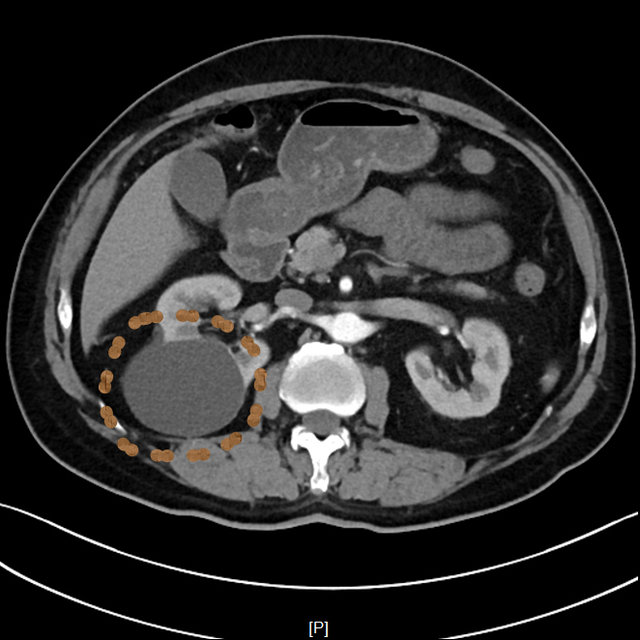

▲患者CT影像

考虑到老赵年事已高,行动不便,王晓明副主任医师当即电话联系泌尿外科,安排其住院,并行CTU(尿路造影)、血凝等术前常规检查,第二日在局部浸润麻醉下进行超声引导下肾囊肿穿刺抽液硬化治疗。